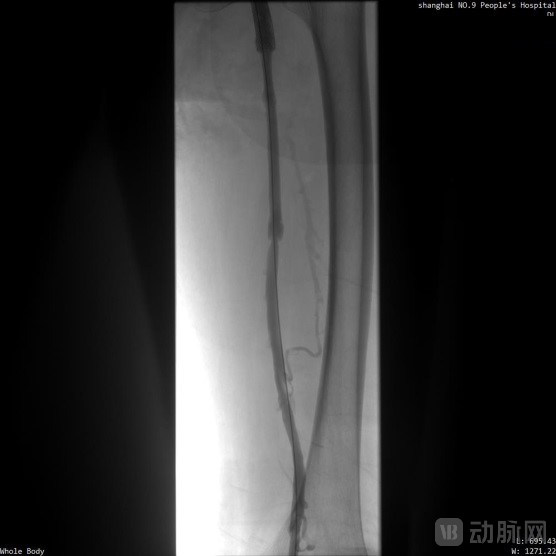

取栓术前管腔造影

取栓术后管腔造影